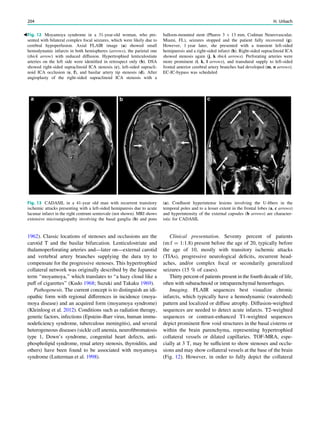

Fig. 1 Digital photogram of the brain surface before placement of a

Fig. 2 Epileptogenic lesion and symptomatogenic zone. A 40-year-

(a, arrow). Simultaneous video and EEG recordings from interhemi-

Clinical symptoms start around 1 s afterwards (d, asterisk)